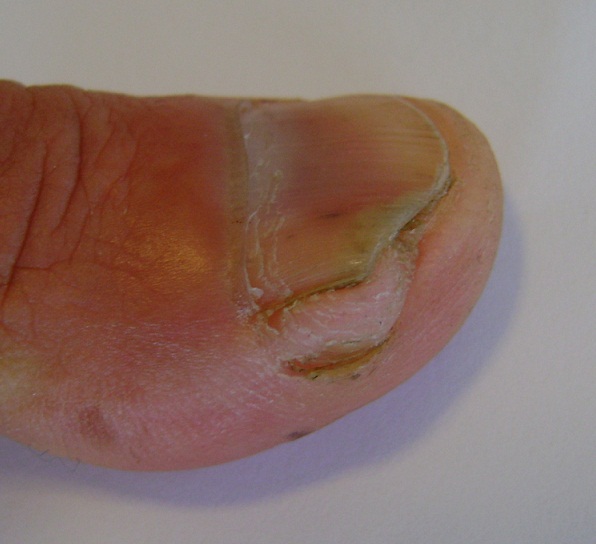

Le neurofibrome est une tumeur bénigne dont l’origine est la prolifération des cellules périphériques des gaines nerveuses. Il peut se retrouver soit dans le cadre de la neurofibromatose ou soit sous forme d’une tumeur solitaire. Jusqu’à présent, moins de 10 cas de neurofibrome sous-unguéal solitaire non associé à la maladie de Von Recklinghausen ont été rapporté dont 1 seul cas chez le sexe masculin. Sa croissance est généralement lente, peu symptomatique rendant son diagnostic difficile. Son diagnostic repose sur l’examen histologique et son excision chirurgicale complète représente le traitement de choix. Nous rapportons le cas d’un patient âgé de 54 ans, sans antécédents pathologiques particuliers, qui présente depuis 2 ans, une tumeur sous unguéale du pouce droit, augmentant progressivement de taille. A l’examen, cette tumeur était de couleur chaire soulevant partiellement la tablette unguéale, sensible à la palpation, de consistance molle, de 1cm de grand axe. Le reste de l’examen dermatologique et somatique étaient sans anomalies. Plusieurs diagnostics ont été évoqués : un fibrokératome, un fibrome, un fibromyxome et un neurofibrome. Une exérèse complète de la tumeur était réalisée et l’examen histologique était en faveur d’un neurofibrome solitaire du pouce droit.